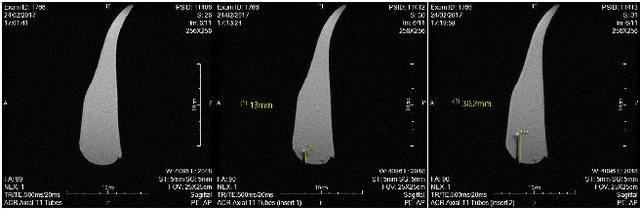

Abstract:This paper introduces a new type of nonmagnetic actuator for MRI interventions. Ultrasonic and piezoelectric motors are one the most commonly used actuators in MRI applications. However, most of these actuators are only MRI-safe, which means they cannot be operated while imaging as they cause significant visual artifacts. To cope with this issue, we developed a new pneumatic rotary servo-motor (based on the Tesla turbine) that can be effectively used during continuous MR imaging. We thoroughly tested the performance and magnetic properties of our MRI-compatible actuator with several experiments, both inside and outside an MRI scanner. The reported results confirm the feasibility to use this motor for MRI-guided robotic interventions.